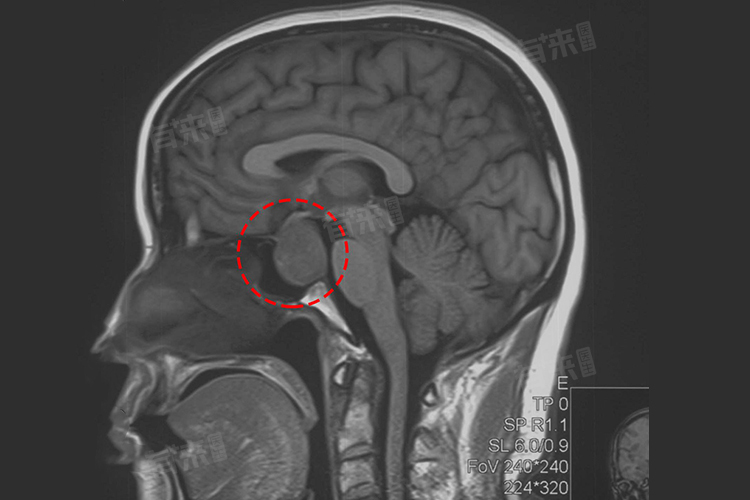

若垂体大腺瘤体积较小,未压迫周围重要结构,激素分泌影响也较轻微,可能仅出现一些不典型症状,如轻微头痛,对身体整体影响相对较小。但当瘤体增大,压迫视神经,会导致视力下降、视野缺损,严重影响生活质量;若压迫下丘脑等结构,还可能引发内分泌紊乱,出现如甲状腺功能异常、肾上腺皮质功能减退等症状,此时病情较为严重。此外,若瘤体过度分泌激素,如生长激素,会引发肢端肥大症;分泌促肾上腺皮质激素,可导致库欣综合征,严重影响全身代谢及多脏器功能。

手术治疗是常见手段,对于多数垂体大腺瘤,通过手术切除瘤体,可解除对周围组织的压迫,恢复正常结构与功能。手术方式根据瘤体位置、大小等选择,如经鼻蝶窦手术,创伤相对较小。放疗适用于术后残留、复发或不适合手术的患者,利用放射线抑制肿瘤细胞生长。药物治疗则针对一些功能性垂体大腺瘤,通过药物调节激素水平,控制病情发展。

- 定期复查与随访情况:定期复查与随访对垂体大腺瘤预后较为重要,通过影像学检查如磁共振成像,监测肿瘤有无复发;检测激素水平,评估内分泌功能恢复情况。若能及时发现肿瘤复发或内分泌异常,调整治疗方案,可改善预后。患者依从性好,按时复查,积极配合治疗,预后更佳。